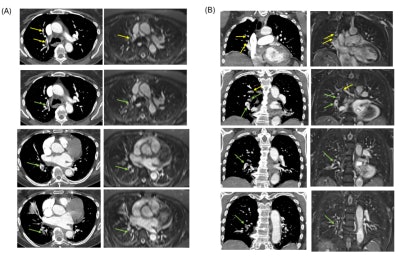

Axial (A) and Coronal (B) CTPA show multiple partial intraluminal filling defects along the course of the right middle lobar segmental branches (medial segment) (yellow arrow) and lower lobar and postero-medial segmental branches (green arrow). Note the low-signal filling defects on the axial and coronal 0.55T MRI sequence.Axial (A) and Coronal (B) CTPA show multiple partial intraluminal filling defects along the course of the right middle lobar segmental branches (medial segment) (yellow arrow) and lower lobar and postero-medial segmental branches (green arrow). Note the low-signal filling defects on the axial and coronal 0.55T MRI sequence. Caption and image courtesy of Rudy Rizzo, PhD, University of Michigan, and ISMRM

Two cardiothoracic radiologists evaluated the low-field MRI first, followed by the CTPA diagnostic reference. Using a 5-point Likert scale, both readers reported "very good overall image quality" for MRA that was comparable to CT images.

Both readers also agreed on the ability to track pulmonary arteries to the segmental level, with one reader confident up to the subsegmental level. Finally, both readers expressed high confidence in distinguishing pulmonary veins from arteries and in making the diagnosis.

While CTPA images displayed higher resolution, sharper details, and a more homogeneous white blood pool -- attributed to the imaging contrast -- MRA images showed well-opacified pulmonary arteries, though reduced resolution along the axial dimension was observed due to the large slice thickness, the team noted.